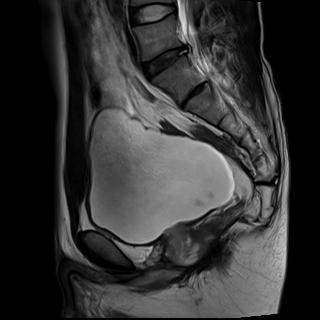

上圖為直腸癌術(shù)后復(fù)發(fā)患者。

MRI主要根據(jù)直腸壁的形態(tài)、厚度異常,腔內(nèi)軟組織塊影來診斷直腸癌,應(yīng)用直腸內(nèi)線圈、脂肪抑制脈沖序列進(jìn)行動(dòng)態(tài)增強(qiáng)檢查,獲取高分辨力的T1和T2加權(quán)像,可以清晰顯示直腸壁的各層結(jié)構(gòu),有助于確定腫瘤范圍、有無局部淋巴結(jié)轉(zhuǎn)移,以及顯示腹膜的種植轉(zhuǎn)移病灶。注意矢狀位圖像還可用于評(píng)估骶骨受累情況。參照直腸癌病理T分期,高分辨MRI的各期表現(xiàn)為:T1期表現(xiàn)為黏膜和黏膜下層的增厚,但固有肌層完整,T1加權(quán)成像增強(qiáng)呈不均勻強(qiáng)化,T2加權(quán)成像上腫瘤信號(hào)低于高信號(hào)的黏膜下層。T2期腫瘤組織進(jìn)入但未穿過固有肌層,肌層變薄但肌層與周圍脂肪交界面完好。T3期表現(xiàn)為腫瘤信號(hào)超出肌層,深入腸周脂肪,肌層與周圍脂肪的界面消失。T4期表現(xiàn)為腫瘤信號(hào)明顯侵入周圍鄰近組織器官。

直腸癌的MRI檢查還可鑒別腫瘤術(shù)后復(fù)發(fā)與瘢痕。復(fù)發(fā)腫瘤在T1加權(quán)像上常為低信號(hào),增強(qiáng)掃描呈中等強(qiáng)度,在T2加權(quán)象上為中等度高信號(hào);而纖維化或瘢痕呈低信號(hào)。有時(shí)二者鑒別困難,可以結(jié)合患者的臨床資料進(jìn)行綜合判斷,若患者的CEA值升高,出現(xiàn)骶骨前疼痛,臨床可考慮為腫瘤復(fù)發(fā)。